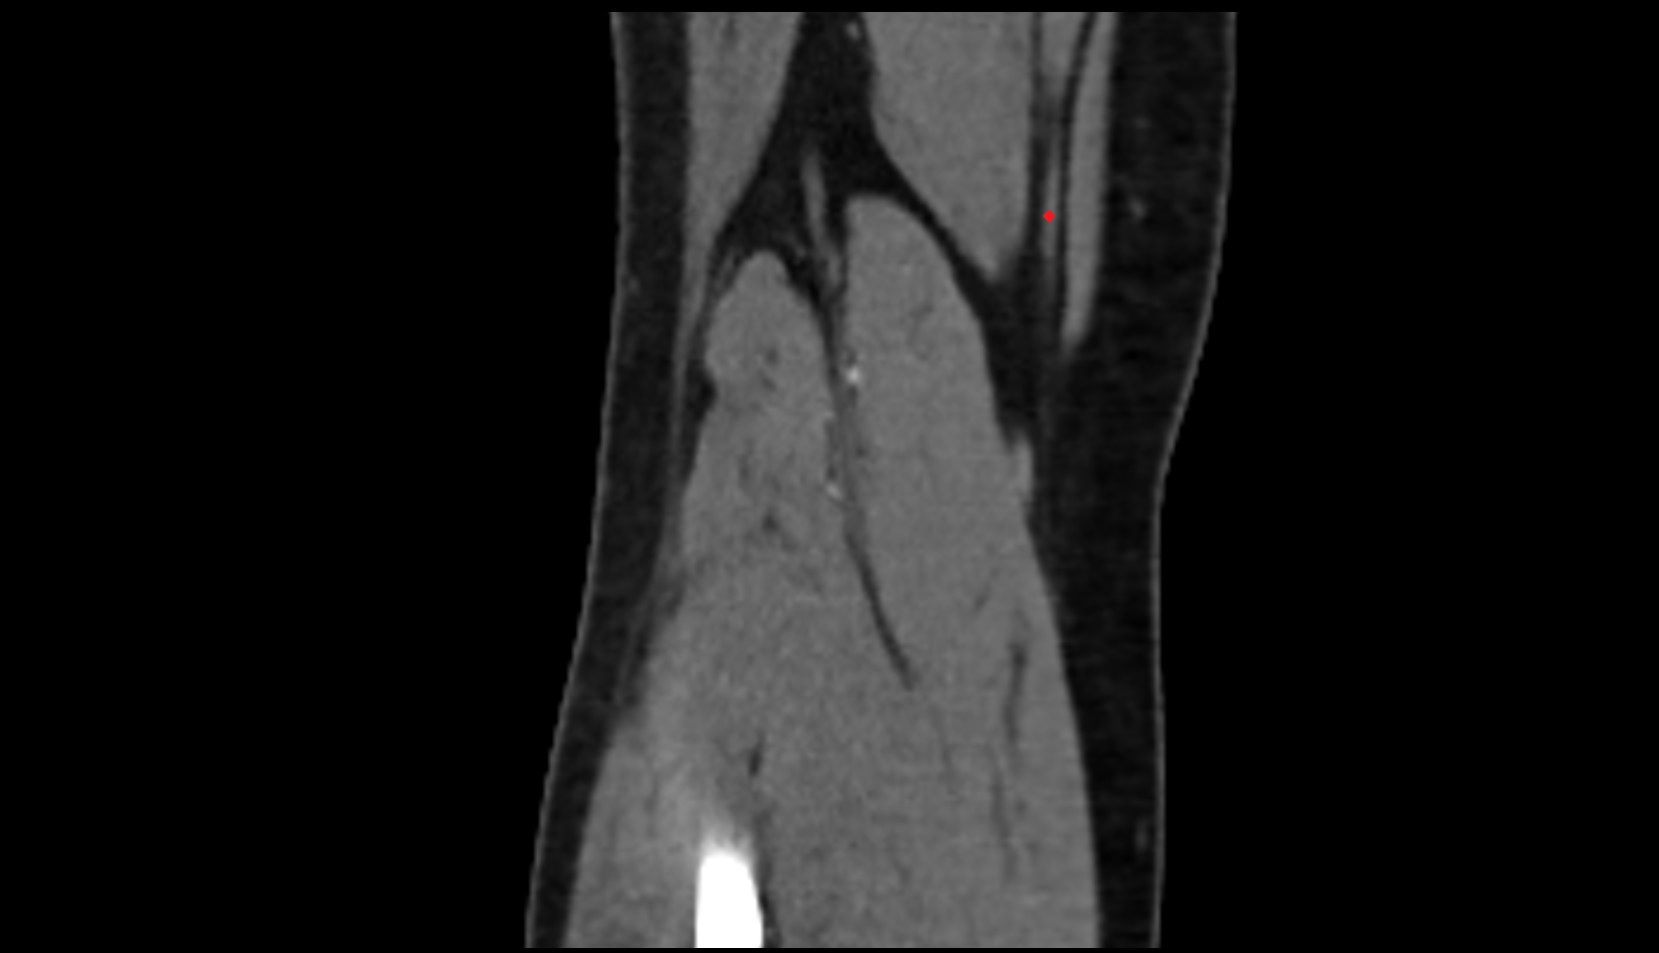

- Knee Joint